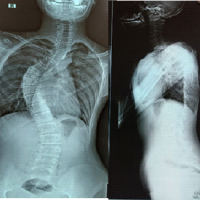

A 52-year-old male presented with right knee medial pain for 3 months, exacerbated by stair climbing and squatting, associated with popping and locking sensations. On physical examination, the range of motion (ROM) of the right knee is mildly limited by pain during flexion, medial joint line tenderness, and a positive McMurray test for the posterior horn of the medial meniscus. Gross effusion is noted, with aspiration yielding 40 cc of serous fluid containing chondral debris. Radiographs and scanography reveal no significant mechanical axis deviation, and the knee appears grossly normal on imaging. He denies any recent trauma but has a history of an old femoral fracture treated with surgical fixation and subsequent implant removal (Fig. 1).

Figure 1: Full-length frontal radiographs of both lower extremities show no significant mechanical axis deviation.